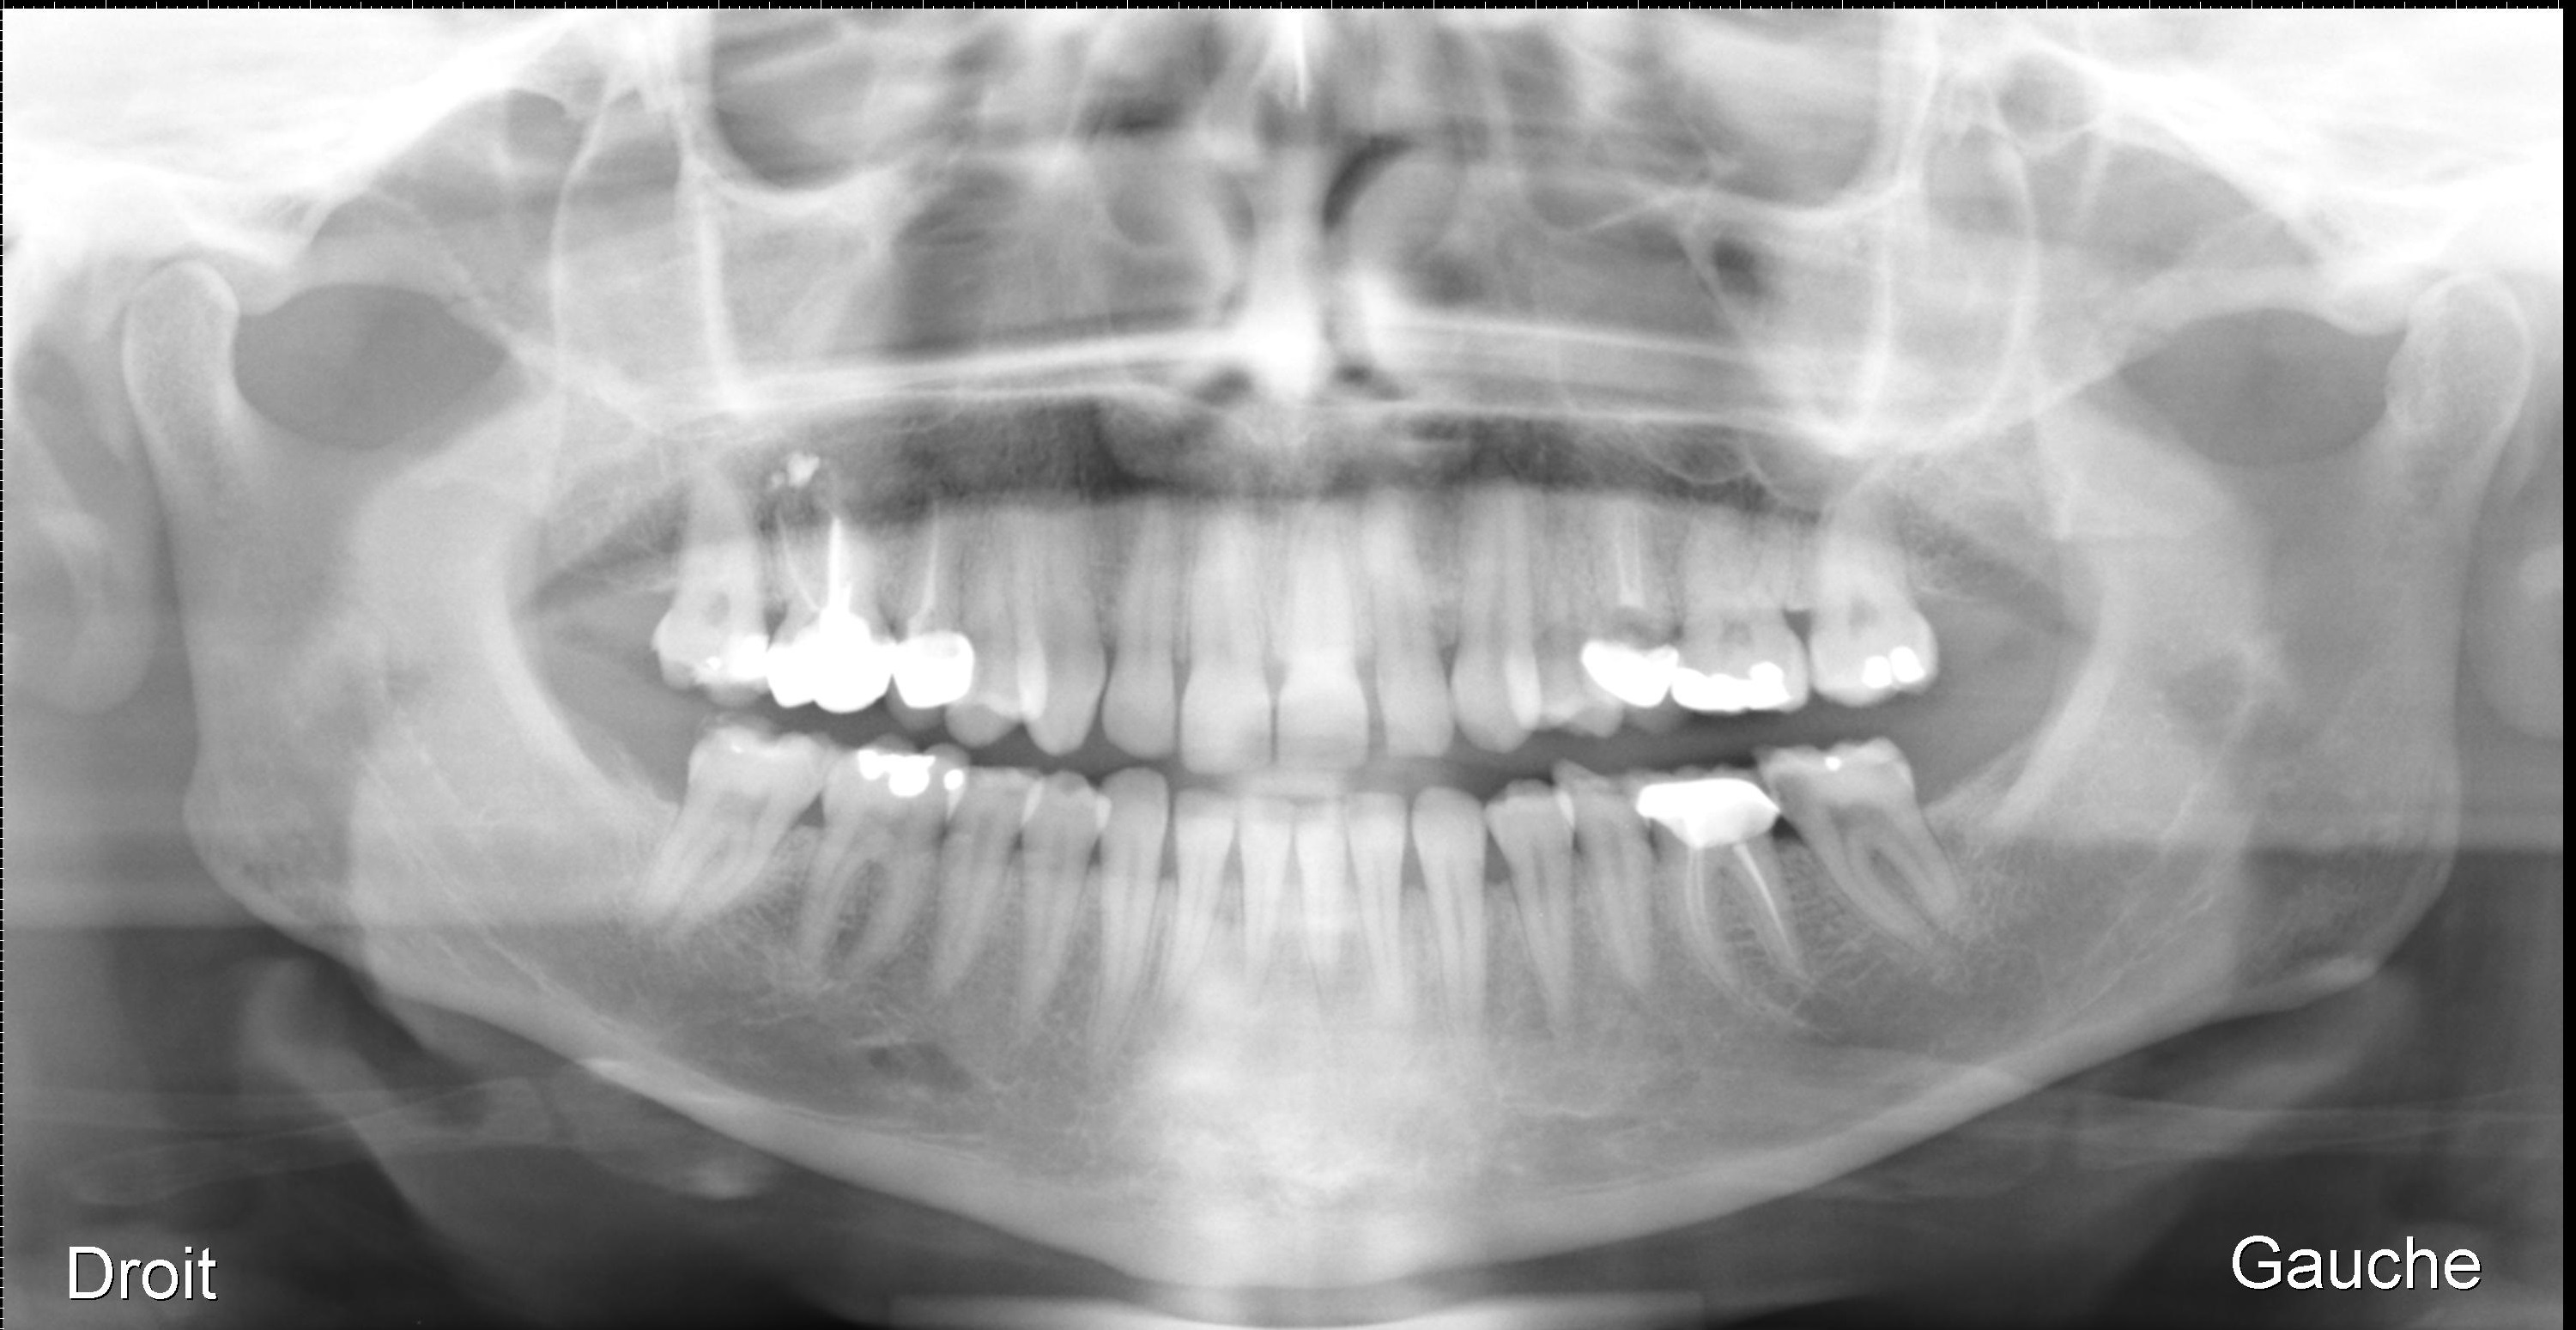

Les radiographies panoramiques (ortho-pantomogrammes), donnent un bonne vue d’ensemble sur toutes les dents et les germes mais sont un peu floues au niveau des détails et de la structure osseuse.

sur la panoramique on peut détecter :

1- abcès péri apical.

2- cellulite.

3-l’âge dentaire.

4-sinusite.

5- fracture sous condylien.

un abcès et une cellulite ne se voient pas à la radio ce sont des tissus mous; on peut voir une ostéite, ou un granulome ou un kyste qui peuvent accompagner au niveau osseux

On peut avoir une idée de l’age dentaire par le stade d’évolution des germes des dents

Une sinusite peut se voir s’il y a une différence d’opacité des sinus; si elle est bilatérale c’est plus difficile.

les fractures sous condyliennes et mandibulaires se voient.